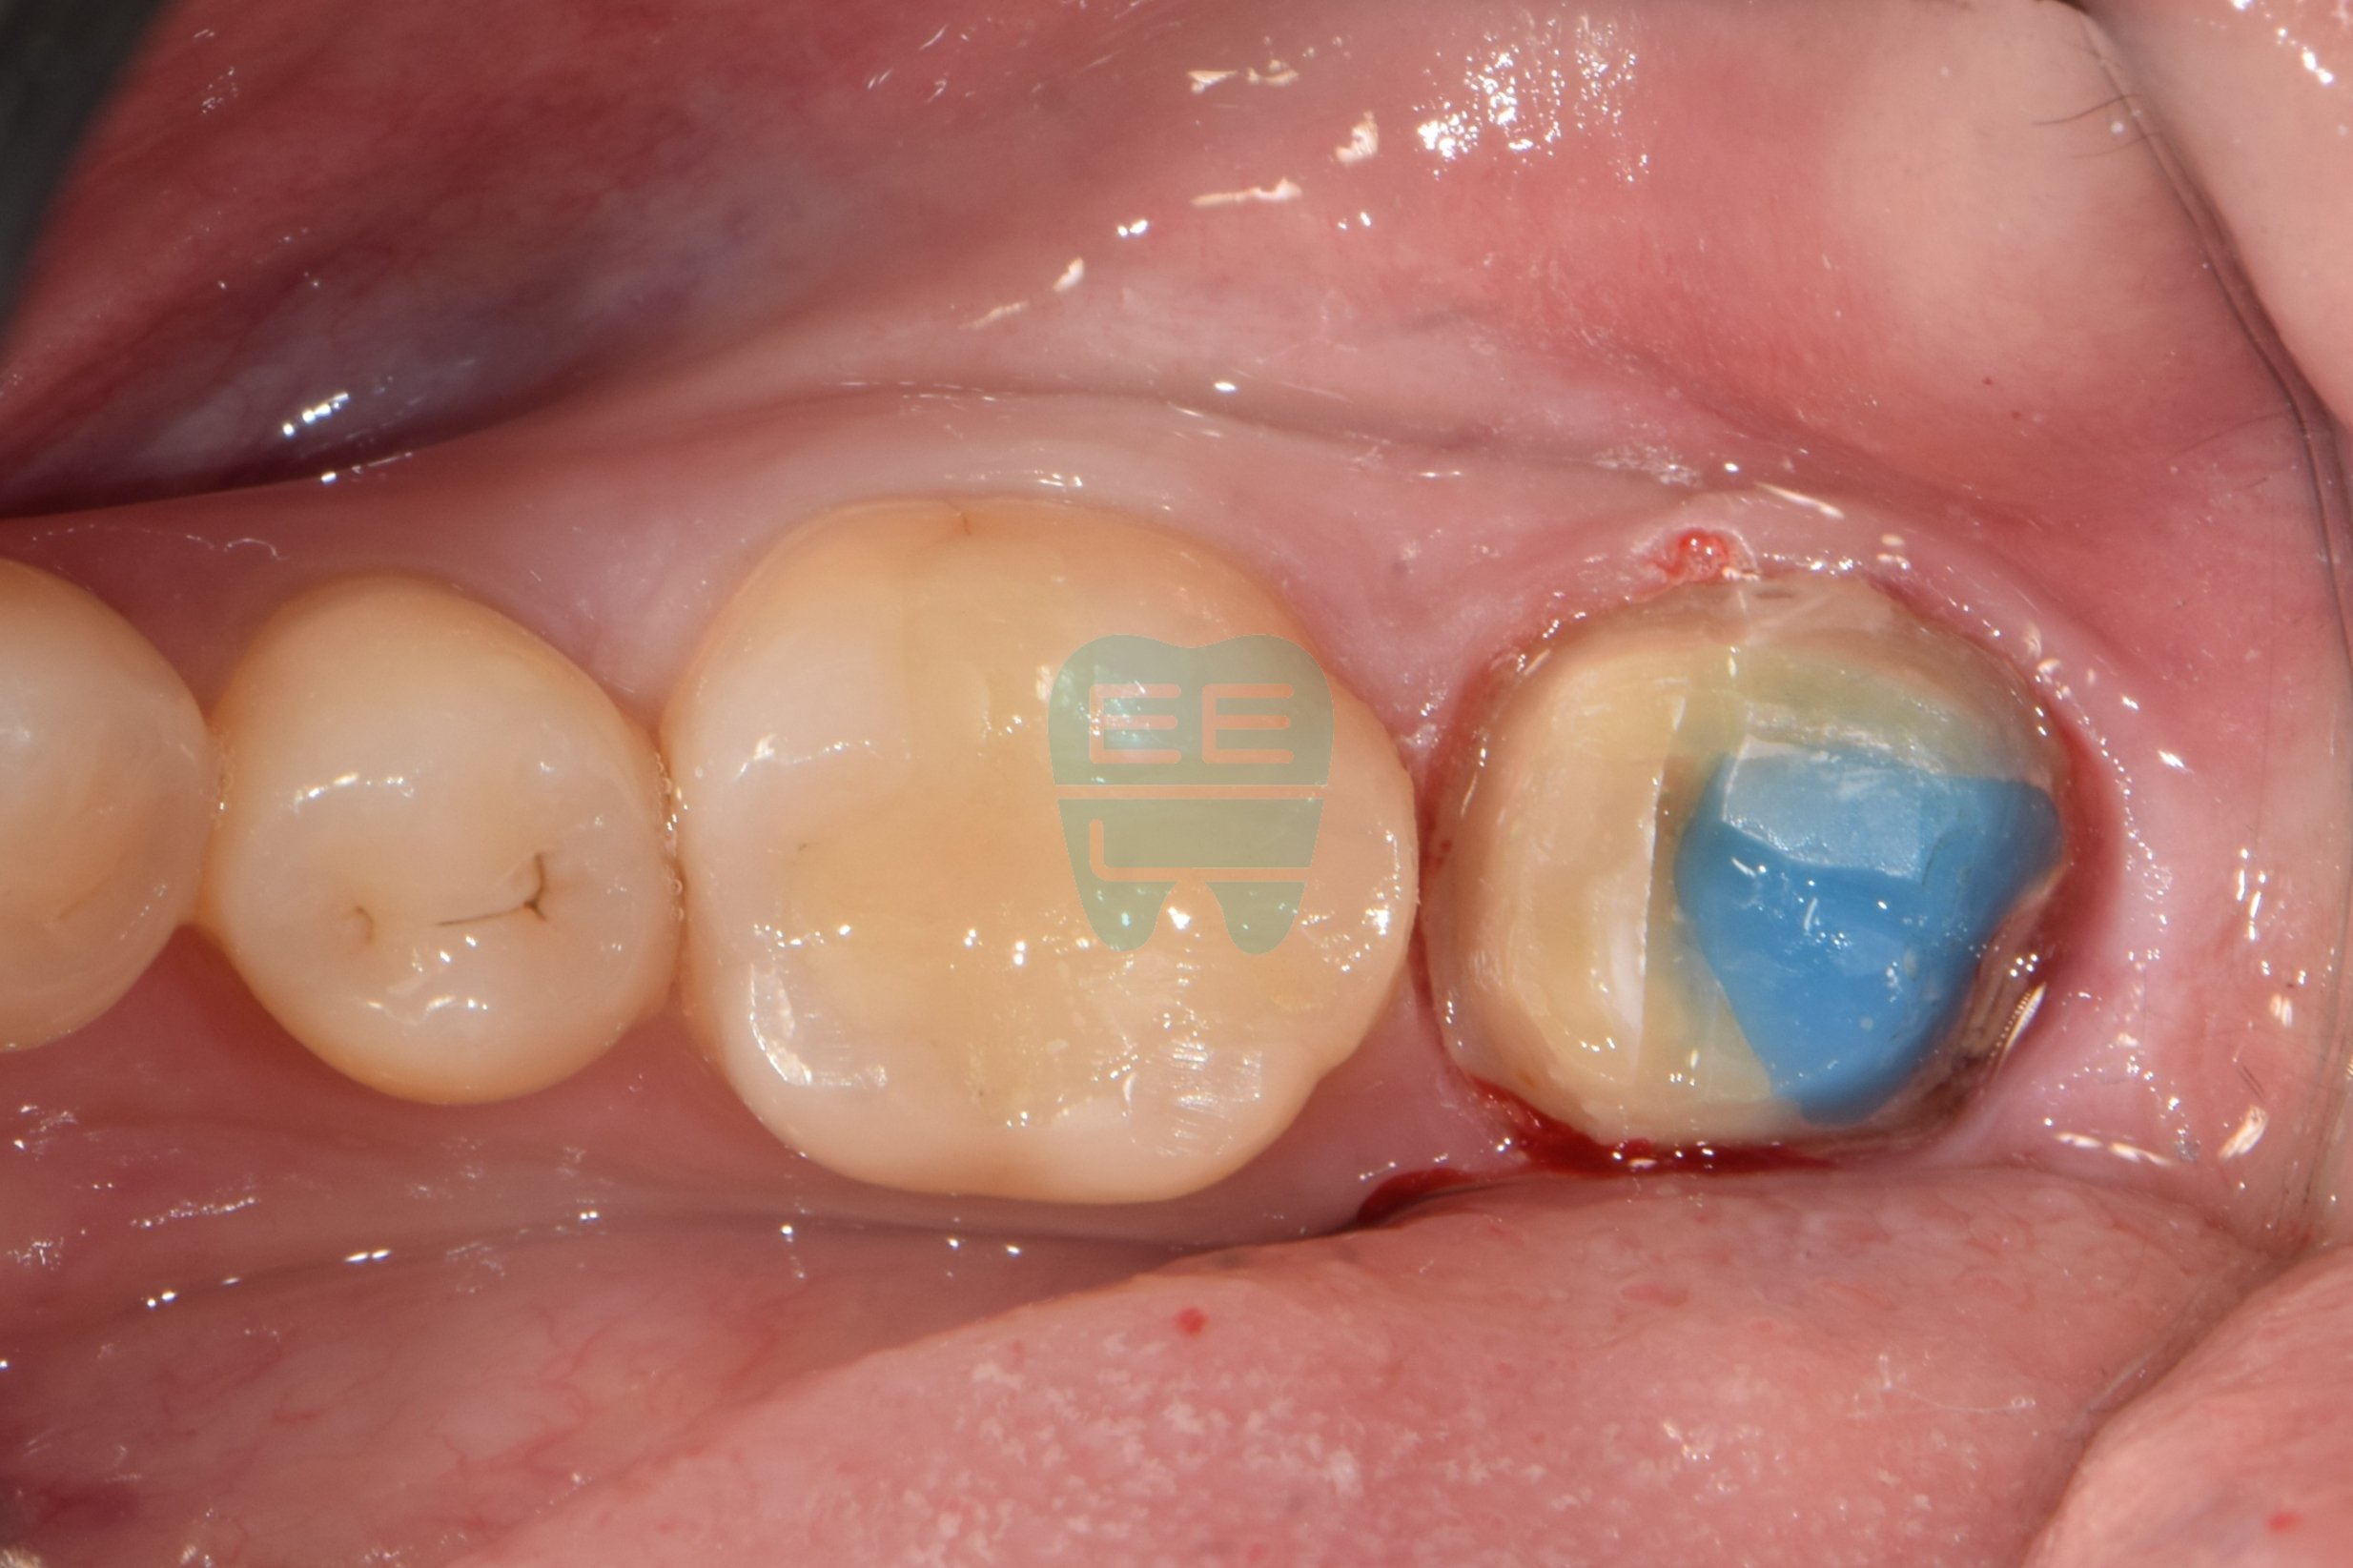

크라운 하방 2차우식 치료를 위한 레진코어 빌드업 방법

초진상태로 찝찝한 냄새가 나신다 하심크라운 제거후 상태로 파란색 코어가 관찰됨코어 제거후 상태로 원심 2차우식으로인한 leakage로인한 악취로 진단함충치와 레진코어를 모두 제거한 상태러버댐과 원심 격리를 위한 매트릭스 밴드를 장착중인 모습러버댐 하에 원심 레진wall을 형성한 모습

사진 2